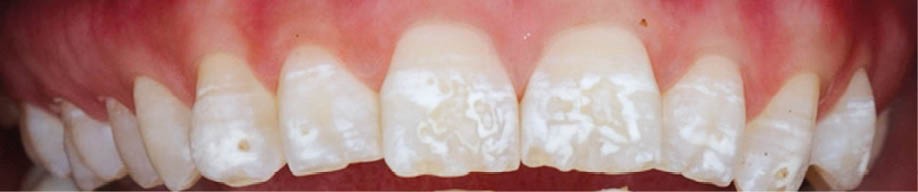

L’émail dentaire, tissu le plus dur et le plus minéralisé du corps humain, peut être affecté par des anomalies génétiques inscrites dans le génome de l’individu, mais également par des facteurs environnementaux. Ces facteurs sont multiples et signent un événement ou une exposition à un xénobiotique au cours de la vie de l’individu. Parmi les atteintes développementales acquises de l’émail, outre la fluorose, figurent les hypominéralisations à type de MIH (Molar Incisor Hypomineralization). Celles-ci sont observées de manière caractéristique sur une ou plusieurs premières molaires permanentes et potentiellement les incisives permanentes éruptant vers l’âge de 6 à 7 ans d’après la description qui en a été faite en 2001 [3] (fig. 1 à 3). La prévalence est importante, la MIH touchant, selon les méta-analyses les plus récentes, plus de 13 % des individus dans le monde, et peut varier selon les études et les pays dans lesquels elles sont menées [4, 5]. Son étiologie est encore incertaine, mais la communauté scientifique s’accorde sur le fait qu’elle serait multifactorielle et notamment en lien avec la survenue d’une hypoxie à la naissance, de fortes fièvres, des épisodes infectieux de la sphère ORL dans la petite enfance ou encore avec une prédisposition génétique [6]. Cette pathologie aurait toujours existé, mais sa prévalence semble être en nette augmentation. Peu d’études ont été réalisées sur cette évolution dans le temps [7].

Les cellules responsables de la synthèse de l’émail, les améloblastes, disparaissant au moment de l’éruption des dents, les défauts de structure et de qualité de l’émail sont irréversibles. L’émail dentaire est ainsi capable d’enregistrer des événements environnementaux ayant eu lieu lors de sa formation. Ces défauts sont donc en quelque sorte le disque dur des contaminations que les améloblastes ont subies. De ce fait, le défaut de minéralisation caractérisant le MIH est le signe d’une exposition environnementale délétère intervenue au cours de la période périnatale (période d’amélogenèse des dents impactées par le MIH), soit environ 5 ans avant leur éruption (fig. 4).